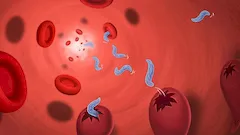

Zimnica / Malaria (Plasmodium)

Zimnica, inaczej malaria (plasmodiosis) jest bardzo poważna infekcją pasożytniczą. Wyróżniamy około 6 gatunków zarodźców malarii:

Plasmodium falciparum (zarodziec sierpowaty),

Plasmodium vivax (zarodziec ruchliwy),

Plasmodium malariae (zarodziec pasmowy),

Plasmodium ovale (zarodziec owalny),

Plasmodium knowlesi (zarodziec małpi),

Plasmodium berghei.

Najnowsze badania dowodzą, że liczba ta może być większa.

Zakażenie malarią staje się coraz powszechne. Zasięg jej występowania poszerza się coraz bardziej i nie jest to już obecnie choroba jedynie tropikalna. Malarią można się zarazić w krajach basenu Morza Śródziemnego,

np. we Włoszech, Grecji, Chorwacji, czy Turcji. Zakażenie jest obecne powszechne także na terenie Polski.

Drogi zakażenia i rozwój pasożytów.

Malaria przenoszona jest przez samice komarów widliszków z rodzaju Anopheles. Cykl rozwojowy komara widliszka jest uzależniony od warunków klimatycznych: w temp. >30st. C trwa 7 dni, a w temp. 20st. C powyżej 3 tygodni. Poniżej 16st. C dochodzi do zatrzymania cyklu rozwojowego pasożytów. Komary potrzebują do rozmnażania się środowiska wodnego, w którym składane są jaja. Do zakażenia może dochodzić także przez transfuzje krwi lub może być przekazane z matki na dziecko przez łożysko. Po ukąszeniu przez komara zakażenie początkowo przechodzi w fazę uśpienia. Po pewnym czasie rozpoczyna inwazję na erytrocyty, gdzie zarodźce rozmnażają się. Obecność zarodźca malarii powoduje niszczenie czerwonych krwinek. W organizmie samicy komara widliszka dochodzi do licznych podziałów, w wyniku których powstają tysiące form inwazyjnych dla człowieka, które dostają się do układu krwionośnego człowieka poprzez ukąszenia komara. Następnie większość z nich przedostaje się do wątroby.

Nie występują wówczas zwykle żadne objawy choroby, choć lekkie poty nocne mogą się pojawiać. Po około dwóch tygodniach dojrzałe formy zarodźca malarii pękają uwalniając do krwiobiegu merozoity. Są to formy przetrwalnikowe, które mogą się uaktywnić w okresie od kilku tygodni do kilku lat, powodując nawrót choroby. Z tych i innych względów niektórzy uważają malarię za chorobę nieuleczalną, a jedynie zaleczalną.